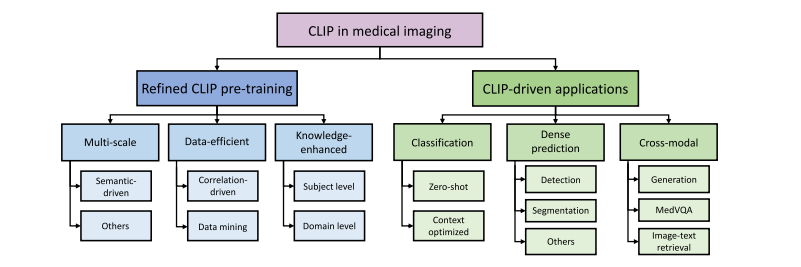

尽管在过去十年中视觉智能领域取得了重大进展(何恺明等人,2016;塔尔瓦宁和瓦尔波拉,2017;多索维茨基等人,2020;刘等人,2021,2022b),但视觉模型通常仅在视觉模态的注释和任务上进行训练(龙内贝格尔等人,2015;何恺明等人,2017;伊森塞等人,2021;何恺明等人,2021)。尽管其中一些方法已经达到了人类水平的性能,但由于缺乏与人类认知的对齐,它们在分布外的性能仍远不能令人满意(彼得森等人,2019;巴特勒迪等人,2020;盖尔霍斯等人,2020;彼得斯和克里格斯克特,2021)。相比之下,文本监督的形式在语义上自然丰富,并且相应的语言模型,尤其是如今的大型语言模型(图夫龙等人,2023;熊等人,2023;张等人,2023a),通常包含大量的人类水平知识。因此,将文本监督整合到视觉任务中是很直观的想法。 受对比预训练的启发,拉德福德等人(2021)提出了对比语言 - 图像预训练(CLIP),它从文本监督中学习可解释的视觉表示。与大多数仅针对视觉的对比预训练方法(陈等人,2020a;卡龙等人,2021;兹邦塔尔等人,2021)不同,CLIP 同时利用了视觉和语言信息。具体来说,它将文本字幕视为图像的一种语言视角,并期望它与图像在本质上是一致的。因此,它在潜在空间中尽可能拉近成对的图像和文本表示。通过这种方式,图像 - 文本对通过 CLIP 的视觉和文本编码器进行对齐,从而大量的知识被编码在视觉编码器中。受益于图像 - 文本对齐,CLIP 从文本监督中学习了广泛的知识,并已被证明在许多领域都很有用,包括图像生成(温克等人,2022;拉梅什等人,2022;于等人,2022;龙巴赫等人,2022)、分割(李等人,2022a;饶等人,2022;罗等人,2023)、检测(班加拉特等人,2022;林和龚,2023)和分类(周等人,2022b,c;王等人,2023b)。 最近,CLIP 在医学成像领域也受到了越来越多的关注(埃斯拉米等人,2021;王等人,2022e;金等人,2024)。图 1 的左图展示了医学成像领域中与 CLIP 相关论文的增长趋势,从 2021 年下半年到 2023 年下半年呈现出数倍的增长,尤其是在 2023 年呈现出蓬勃发展的趋势。这可以归因于它能够使神经网络与人类认知对齐,满足了医疗保健领域人工智能对可解释性的需求(劳里岑等人,2020;乔亚和关,2020;谢等人,2021)。尽管先前的研究试图通过额外的专家级注释来提高可解释性,例如边界框(罗等人,2022;欧阳等人,2020;谷田等人,2023;米勒等人,2023)和分割掩码(梅塔等人,2018;周等人,2019),但收集这些注释既费力又耗时(拉希米等人,2021;王等人,2022b;曲等人,2023),这使得它们难以大规模应用。相反,在临床实践中由医学专业人员常规生成和收集的文本报告(黄等人,2021;王等人,2022a;谢等人,2023)以很少的额外成本提供了有价值的专家级知识,这使得 CLIP 成为一个更有前景的解决方案。 动机:尽管许多研究致力于为医学图像分析定制 CLIP,但这种定制带来了一些仍未解决的新挑战。为了鼓励和促进医学成像领域中基于 CLIP 的研究,对现有文献进行综述将是有益的。因此,我们广泛回顾了该领域 200 多种现有方法,以提供有见地的综述。 搜索策略:我们在包括谷歌学术、DBLP、arXiv 和 IEEE Xplore 等学术平台上进行搜索。利用“CLIP”、“图像 - 文本对齐”和“医学成像”等关键词,我们的初步探索涵盖了各种来源,如高影响力的期刊论文、会议/研讨会论文以及仍在评审中的预印本。我们排除了仅将 CLIP 用作基线方法的研究以及不专注于医学成像的研究。鉴于在稳定扩散(龙巴赫等人,2022)取得成功后,CLIP 文本编码器已成为扩散模型(卡泽鲁尼等人,2023)中的关键组件,我们也排除了主要关注扩散模型而非 CLIP 的论文。此外,手术视频和超声等成像模态通常以视频片段的形式呈现。因此,一些专注于这些模态的研究被错误检索到,即使它们没有使用与 CLIP 相关的技术。这些误检索的研究经过人工审查后被排除,而确实采用了 CLIP 的相关研究则被保留。应用这些选择标准后,我们确定了总共 224 篇用于本次综述的论文。按各自使用的成像模态分类的所选论文分布如图 1 的右图所示,其中基于 X 射线的研究占大多数。 分类方法:为了简化我们对医学成像领域中与 CLIP 相关工作的讨论,在本次综述中,我们将它们分为两类,即(1)改进的 CLIP 预训练和(2)由 CLIP 驱动的应用,如图 2 所示。第一类研究侧重于将 CLIP 的预训练范式从网络爬取的图像字幕对调整为医学图像及其相应的报告。第二类研究倾向于直接采用预训练的 CLIP 模型,以提高深度学习模型在各种临床任务中的可解释性和鲁棒性,例如胸部疾病诊断和多器官分割(蒂乌等人,2022;佩莱格里尼等人,2023;刘等人,2023g)。 相关综述:有一些与我们的综述范围相似的同期综述。 例如,什雷斯塔等人(2023)的一篇综述论文侧重于医学视觉语言预训练。他们的综述与我们的综述之间的区别在于:(1)他们主要探索各种视觉语言预训练架构,包括掩码预测(卡雷等人,2021)、对比(黄等人,2021)、匹配预测(穆恩等人,2022)和混合架构(王等人,2021a),对 CLIP 风格的对比预训练的关注较少;(2)他们主要关注大规模预训练,缺乏对临床任务的讨论。由于缺乏大规模的公共医学图像 - 文本数据集,他们的综述的影响可能有限。相比之下,我们的综述深入探讨了由 CLIP 驱动的应用,由于对数据的要求较低且对现实世界临床任务具有更多价值,这些应用在现实环境中更可行。此外,阿扎德等人(2023)探索了医学成像中的基础模型,他们的综述论文中也包括了 CLIP。与我们的综述论文的主要区别在于,他们主要涵盖仅视觉、仅语言和视觉 - 语言基础模型,而我们专门关注 CLIP,这是一种视觉 - 语言基础模型。此外,他们的综述也缺乏对临床应用的讨论,而我们对此进行了广泛的涵盖。因此,我们的综述(与上述两篇综述论文相比)将在技术和临床应用方面提供更有见地和更深入的综述。 贡献:总之,我们的贡献如下: - 据我们所知,本文是对医学成像中 CLIP 的首次综述,旨在为这个快速发展领域的潜在研究提供及时的总结和见解。 - 我们全面涵盖了现有研究,并提供了一个多层次的分类方法,以满足读者的不同需求。 - 此外,我们讨论了该领域的问题和开放性问题。我们还指出了新的趋势,并提出了进一步探索的未来方向。 论文结构:本文的其余部分组织如下。第 2 节提供了 CLIP 及其变体的初步知识。在第 3 节中,我们从关键挑战和相应解决方案的角度,对如何使 CLIP 适应医学成像领域进行了系统分析。第 4 节涵盖了预训练 CLIP 的各种临床应用,并将由 CLIP 驱动的方法与早期方法/解决方案进行了比较。第 6 节进一步讨论了现有局限性以及潜在的研究方向。我们最后在第 7 节中对本文进行总结。

Fig. 2. Taxonomy of studies focusing on CLIP in the field of medical imaging.

图2. 医学成像领域中专注于对比语言-图像预训练模型(CLIP)的研究分类。